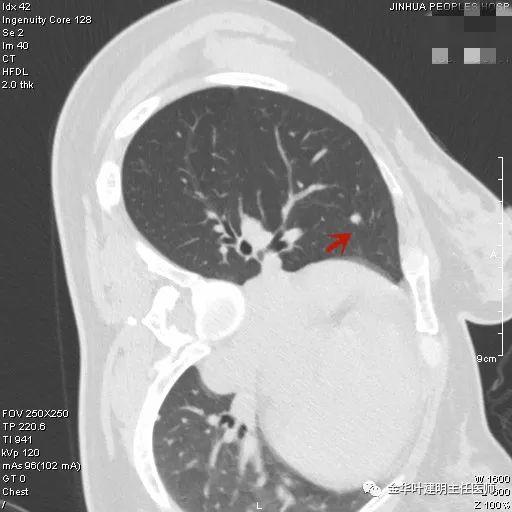

上图示结核。我们发现其有明显的卫星灶,如绿色箭头所示,主病灶处也是周边有模糊区域,病灶整体密度较为均匀(肿瘤容易生长不均致密度欠均匀,显杂乱)。

叶建明谈结节:检查发现肺实性结节怎么办?个人版实用指南